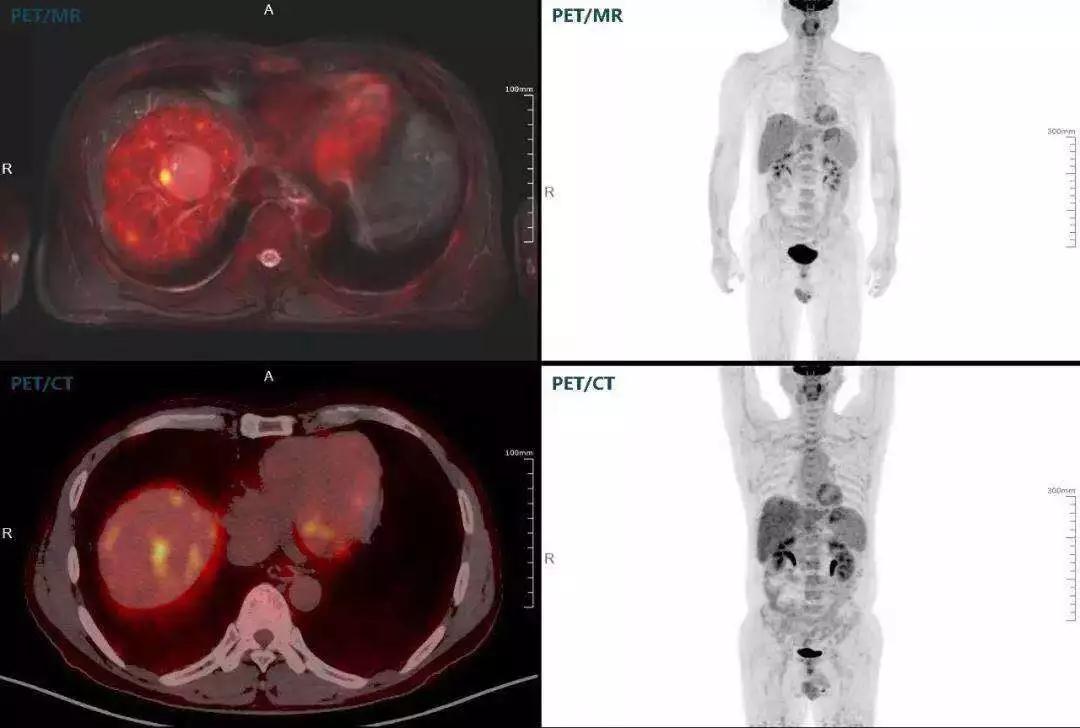

多發(fā)性骨髓瘤

中山醫(yī)院核醫(yī)學(xué)科基于聯(lián)影“時(shí)空一體”超清TOF PET/MR的融合顯像優(yōu)勢(shì),進(jìn)行了大量的臨床掃描,發(fā)現(xiàn)多例由MGUS向多發(fā)性骨髓瘤轉(zhuǎn)變,并從中總結(jié)出了一定的共同征象,未來可能實(shí)現(xiàn)多發(fā)性骨髓瘤的早期篩查。此外,PET/MR在多發(fā)性骨髓瘤的療效評(píng)估方面,也存在顯著優(yōu)勢(shì)。

(男性,53歲。確診多發(fā)性骨髓瘤10月。經(jīng)過7周期VCD方案化療后,現(xiàn)行療效評(píng)價(jià)。)